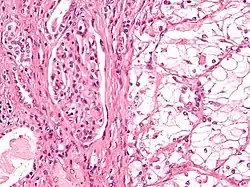

| Micrograph showing the most common type of kidney cancer (clear cell renal cell carcinoma). H&E stain. | |

The most common type of kidney malignancy is renal cell carcinoma,[35] which is thought to originate from cells in the proximal convoluted tubule of the nephron.[15][36] Another type of kidney cancer although less common, is transitional cell cancer (TCC) or urothelial carcinoma of the renal pelvis.[37] The renal pelvis is the part of the kidney that collects urine and drains it into a tube called the ureter.[37] The cells that line the renal pelvis are called transitional cells, and are also sometimes called urothelial cells. The transitional/urothelial cells in the renal pelvis are the same type of cells that line the ureter and bladder. For this reason TCC of the renal pelvis is distinct from RCC and is thought to behave more like bladder cancer.[37] Other rare types of kidney cancers that can arise from the urothelial cells of the renal pelvis are squamous cell carcinoma and adenocarcinoma.[15]